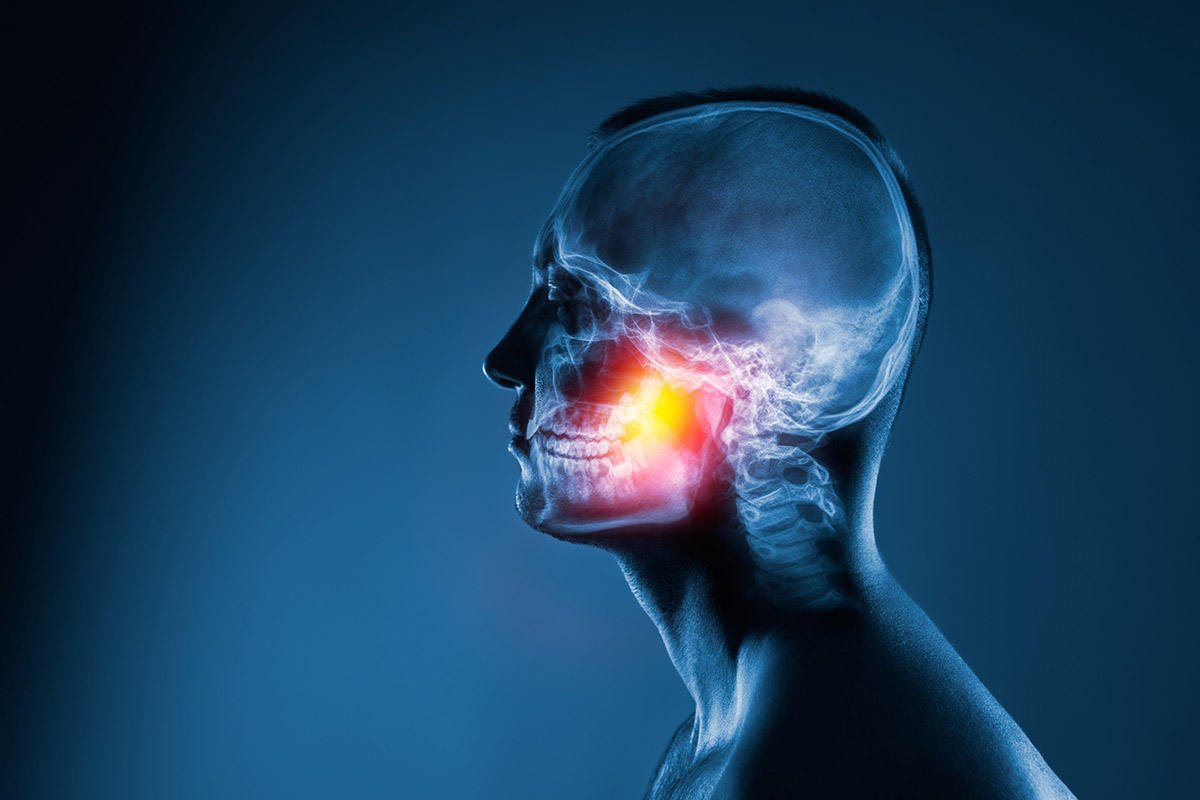

ΤΙ ΠΡΟΚΑΛΕΙ ΠΟΝΟ ΣΤΗ ΓΝΑΘΟ;

Λίγο πολύ, όλοι κάποια στιγμή θα αισθανθούμε από ενόχληση έως πόνο στη γνάθο. Ας δούμε ποιες είναι οι πιθανές αιτίες και πότε πρέπει πραγματικά να μας ανησυχήσει άμεσα.

Πονάς στη γνάθο; Μήπως νιώθεις μια ενόχληση ή μια μόνιμη ένταση; Πιθανότατα τρίζεις ή σφίγγεις τα δόντια σου όταν κοιμάσαι, συνθήκη που ασκεί μεγάλη πίεση στους μυς και την άρθρωση της γνάθου. Γιατί σου συμβαίνει αυτό;

Τι είναι το σύνδρομο Κροταφογναθικής

Σύμφωνα με τον Ιωάννη Γ. Πλιούτα, Ωτορινολαρυγγολόγο, Χειρουργό Κεφαλής και Τραχήλου, ως σύνδρομο Κροταφογναθικής περιγράφεται ένα σύνολο μυοσκελετικών διαταραχών που επηρεάζουν την κροταφογναθική άρθρωση ή τους μασητήριους μυς, ή και τα δύο. Αντιστοιχούν σε πολλές διαφορετικές διαγνώσεις με παρόμοια σημεία και συμπτώματα που επηρεάζουν το σύστημα της μάσησης. Μπορεί να είναι οξείες, επαναλαμβανόμενες ή χρόνιες.